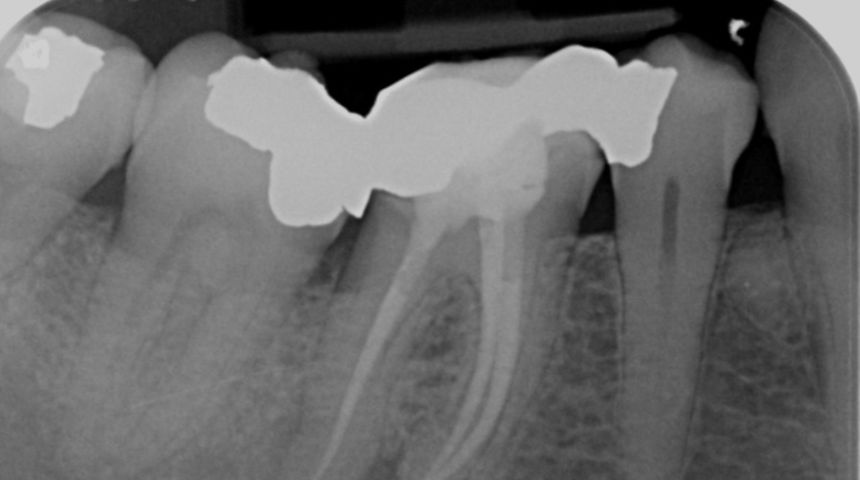

Take a look at some of our recent cases below!